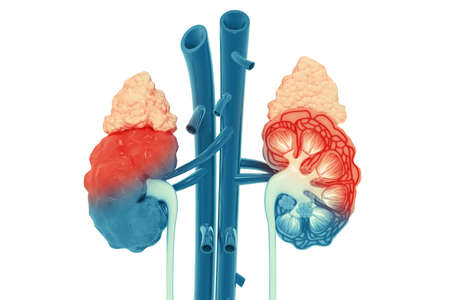

Human kidneys and circulation with a skeleton medical diagram

Human male body with highlighted kidneys showing pain and kidney disease. Digital medical concept illustrating internal organ inflammation.

3 d illustration of human kidneys anatomy (human organs)

Human kidneys on a blue background. Human kidney disease concept, pyelonephritis, kidney stones, infection, copy space, inflammation